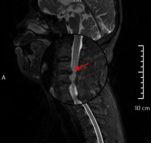

术后复查显示内固定位置良好、椎管减压充分,患者自觉症状明显缓解

为确保手术成功,骨科二区专家团队与湘雅三医院苗惊雷教授紧密协作,在麻醉科和手术室的配合下,成功为患者实施颈前路椎间盘切除术+椎管扩大减压术+植骨融合内固定术,患者术后即感四肢肌力明显改善,目前恢复良好,已顺利出院。